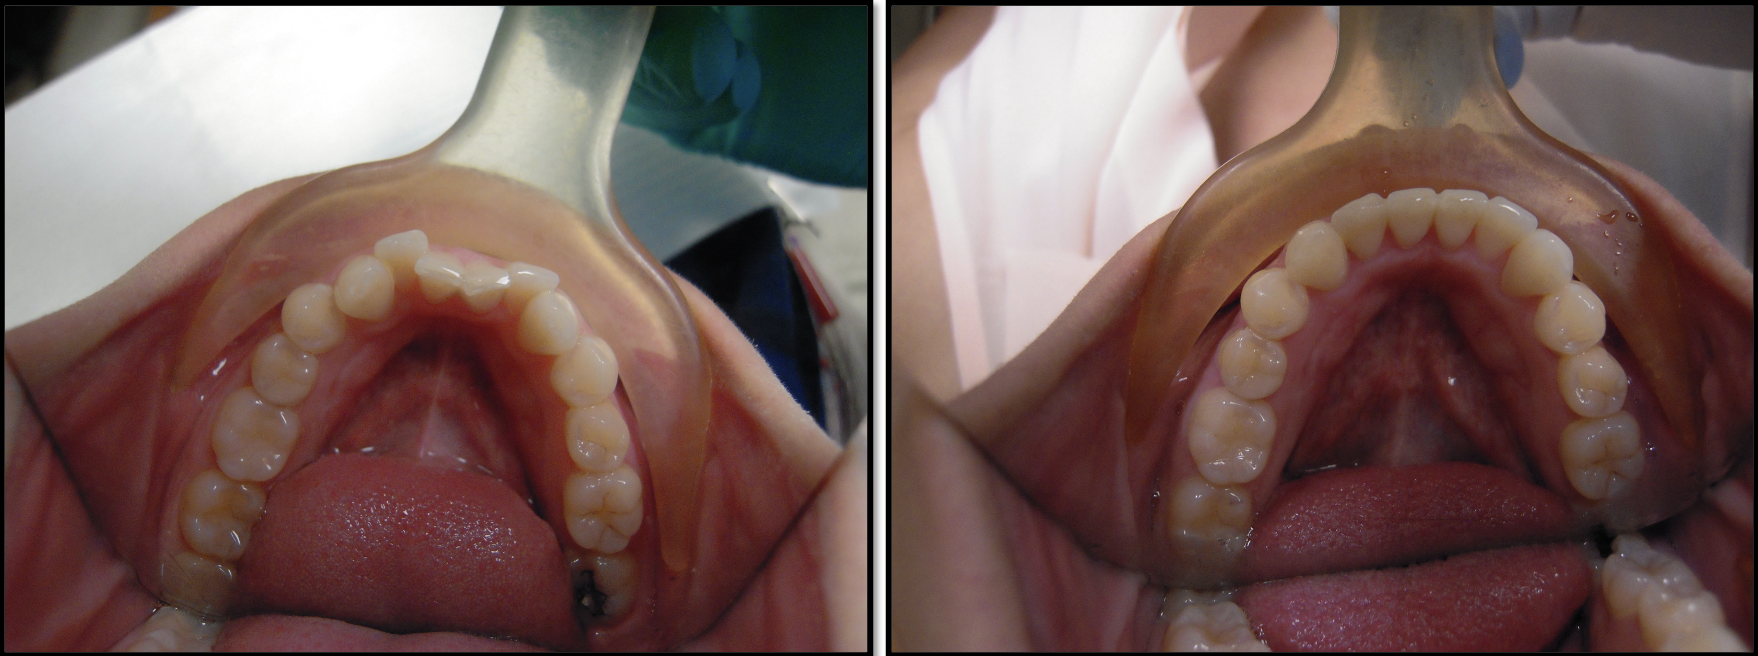

Before & After photos

Welcome to our photo gallery, showcasing the powerful results achieved with "The GOST" process and tools. This innovative approach combines precision and efficiency to deliver exceptional, predictable outcomes for a wide range of dental restorations. As fellow dental professionals, you’ll appreciate the detailed craftsmanship and transformation evident in each before-and-after photo. Explore the impact of The GOST on patient satisfaction and clinical outcomes, and see firsthand how it can enhance your practice by delivering results that meet the highest standards of esthetics and functionality.